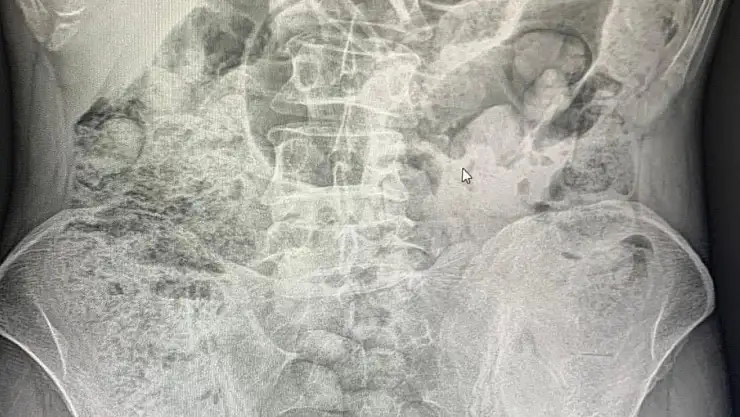

Narkotik ekiplerince yapılan detaylı inceleme ve değerlendirmelerde, şahısların uyuşturucu maddeleri batı illerine sevk etmek amacıyla bedenlerinde, yutma yöntemiyle mide bölgesinde taşıdıkları belirlendi.

Sağlık ekipleri eşliğinde hastaneye sevk edilen şüpheliler, yaklaşık 10 gün süren tıbbi takip ve tedavi sürecinin ardından, cerrahi yöntemler kullanılarak ameliyata alındı. Yapılan operasyonlar sonucunda şüpheli şahısların midelerinden 119 paket halinde toplam 1 kilo 597 gram uyuşturucu madde çıkarıldı.